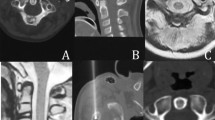

Percutaneous cryotherapy was performed using a cryotherapy delivery system (Cryohit; Galil Medical, Yokneam, Israel), equipped with cryoprobes of 2.0 mm diameter (approximately equal to 14 gauge). A single cryoprobe was inserted coaxially through the access needle (Fig. 2). The access needle was then withdrawn slightly so that the distal 1 cm of the cryoprobe was exposed. A scan was obtained to confirm that the position of the cryoprobe tip was within 5 mm of the inner edge of the nidus (Fig. 3). To prevent skin injury, a small amount of filtered sterile gas (5–10 ml) was injected into the subcutaneous region of the puncture site and a heated sterile water bag was put on the skin near the puncture area. A warming mat was placed under the body of the patient to prevent a substantial decrease in body temperature. Two freeze-thaw cycles were performed for each lesion with a time frame of 8-min freeze, 5-min passive thaw intended for each cycle. During freezing, the cryoneedle tip temperatures reached −175°C (based on a thermocouple measurement).

CT scanning was performed periodically to monitor for changes in surrounding tissues (Fig. 4). CT scanning was performed for lesion localization, needle targeting, and therapy monitoring. Cryoablation may be observed on CT imaging as a hypoattenuating area in the soft tissues and is less conspicuous within bone. Monitoring allows control of the cryoablation zone. There were no direct signs of inadequate coverage. Signs of complications were if the cryoablation zone was extending into adjacent critical structures such as neurovascular bundle, skin, or articular cartilage. Upon completion of the cryoablation, a 3-min active thawing was performed (instilling helium gas into the cryoprobes instead of argon gas), and the probes were removed. As an additional measure to prevent bleeding, a small amount of fibrin glue was inserted into the puncture hole. After the probe was removed, a final CT scan (2 mm thickness) was obtained to check for possible complications such as fracture or hematoma.

Results of the cryoablation are summarized in the Table 1. Percutaneous cryoablation was technically successful in all six patients. The mean time of cryoablation was 18 min (range 12–25 min) for each procedure. There were three cases where the cryoablation zone (ice ball) could be partially visualized within the soft tissues because of a superficial location of the osteoid osteoma and a portion of the active cryoprobe tip was situated within the adjacent soft tissues. The entire procedure duration ranged from 70 to 110 min (mean 90 min). The mean length of in-hospital stay for each admission was 3.5 days (range 3–5 days). All patients tolerated full weight-bearing and could function without limitation within 3 days after the procedure without need for casts or crutches. There were no fractures, hematomas, myoglobinuria, or neurovascular injuries during or immediately after the procedure. One minor complication was observed in a patient who demonstrated moderate fever, discomfort, and had body core temperature of 38°C for 1 day after the operation. These symptoms were relieved after 2 days of physical cooling and administration of acetylsalicylic acid. Significant pain relief was observed in all patients after the ablation. The VAS score averages were 6.57 ± 0.55 pre-procedure, 3.24 ± 0.23 on day 3 post-procedure, 1.54 ± 0.14 on day 7 post-procedure, and 0.57 ± 0.10 on day 30 post-procedure. The results of the t-test showed a statistically significant difference (P < 0.05) between the VAS of patients pre-procedure, and those at 3 days, 1 week, and 1 month post-procedure. The clinical success rate was also 100%, and for all six patients there was no evidence of recurrent symptoms at latest follow-up. No delayed complications (e.g., infection or myoglobinuria) were observed during the follow-up period. No skin changes were identified in the subjects who had superficial lesions treated. No major complications were encountered. For each patient, MRI after the procedure showed an area of signal alteration corresponding to the cryoablation zone (Fig. 5). These post-ablation MRIs depicted no complications that resulted from the procedure. No stress fractures were observed during the 18–36 month follow-up.

We report a case series of six children with osteoid osteoma who were treated successfully, technically and clinically, using percutaneous image-guided cryoablation with intermediate term relief of pain symptoms and no major complications. Prior communications of cryoablation for osteoid osteoma consist of case reports [18, 19]. In one case report there was a pediatric patient with a femoral lesion who was treated with cryoablation under general anesthesia using CT guidance and remained symptom free at 19 months of follow-up [19]. Our series supports these results and extends this work by demonstrating that these procedures can be done without general anesthesia while producing a sustained effect. The post-procedure MRI appearance of cryoablation-treated osteoid osteomas corresponds to that described in the literature for radiofrequency-treated ones [20] with the lesion showing a target-like appearance of the central ablated zone surrounded by a well demarcated band. In our patients, since the scans were done 6 months after the procedure we did not observe a peripheral area of edema, consistent with the time course of edema resolution described post-radiofrequency ablation.